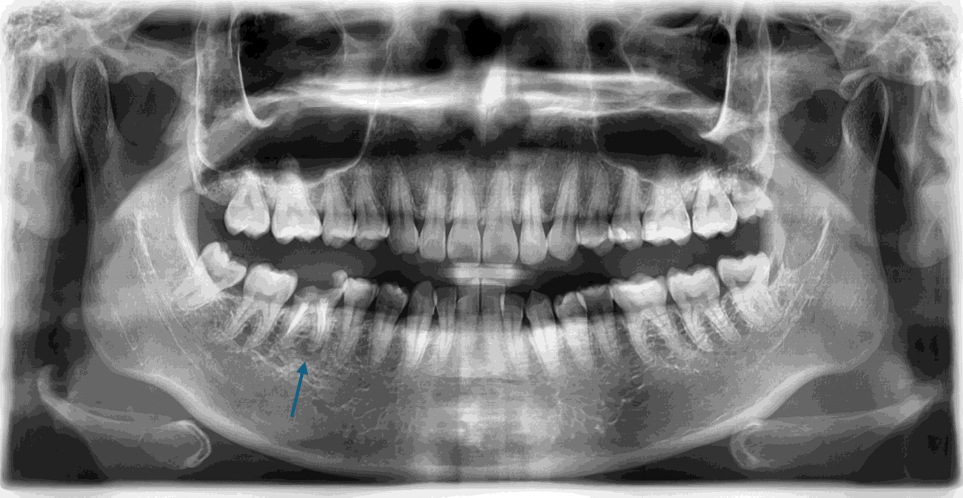

右下第一大臼齒斷裂

治療計畫

右下第一大臼齒拔除, 將右下智齒移植到缺牙區域

術前